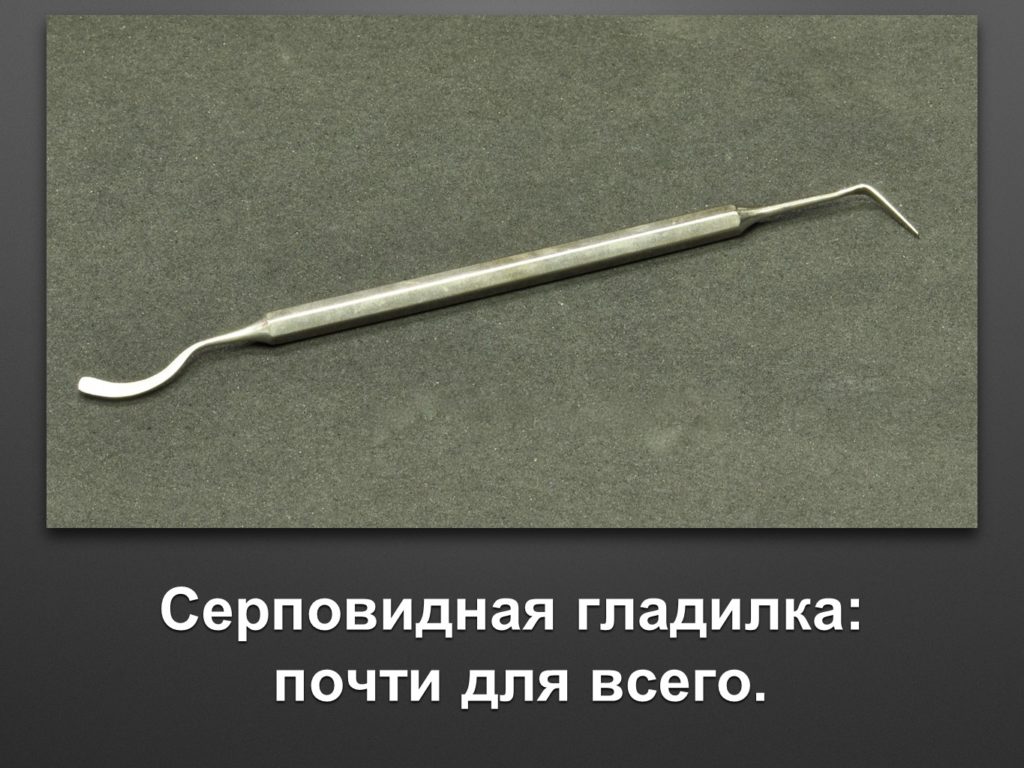

"Выстраданные" наборы инструментов

Все ниже перечисленные инструменты можно приобрести на сайте kohlermed.ru или связаться с нашим менеджером по тел 499-5179401

Все ниже перечисленные инструменты можно приобрести на сайте kohlermed.ru или связаться с нашим менеджером по тел 499-5179401